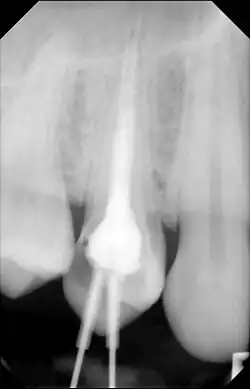

Root canal treatment by Endodontist